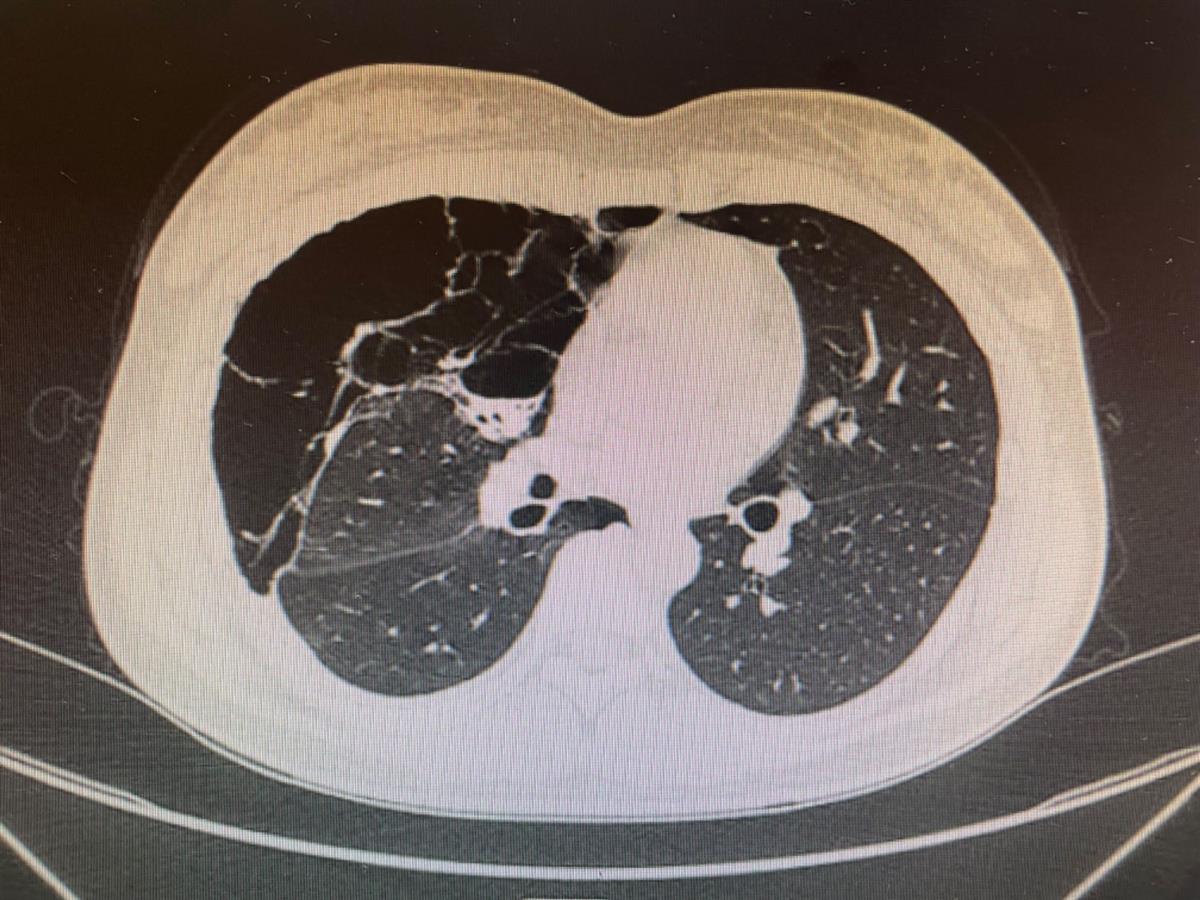

刘女士肺部影像图

胸外科主任医师胡学宁接诊后,通过查看患者影像资料,发现她的肺部有“蜂窝状囊性病变”——右肺囊性大泡几乎占据右侧整个胸腔,且大泡内有积液和积气,隐约可见肺组织被压缩成条索状,这便导致了患者肺不张、呼吸困难。再结合刘女士很年轻,且反复感冒发烧,抗感染治疗长达半个多月仍未得到有效控制,胡学宁怀疑是先天性肺发育畸形,而这种疾病目前尚无明确病因,建议尽早手术治疗,阻止病变发展。刘女士听后十分惊讶,想不到看似简单的“感冒”,牵扯出先天性的畸形,还有癌变的可能。她担心失去右半边肺,在和医生反复沟通后,医生表示尽量把手术损伤降到最低,极力保肺,这给了刘女士很大的信心,她决定积极配合治疗。